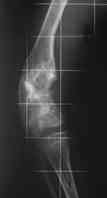

Высылаю вам фото подобной больной, у нее тоже первая попытка до меня была безуспешной.

Нужен аппарат Илизарова стабильный с множеством спиц с напайкой, временной фиксацией колена аппаратом на голени. Наверное, проще первый раз начать с бедра, остеотомию выполнить прямо на уровне перехода очага в дистальный метафиз бедра. Дистракционный остеогенез вызовет перестройку хрящевой ткани в костную. Понадобится еще пара этапов.